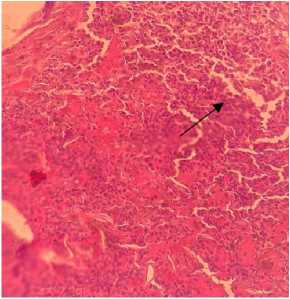

Berdasarkan hasil kultur bakteri dari sampel swab kulit pada anjing kasus yang dilakukan di Balai Besar Veteriner Denpasar ditemukan bahwa adanya koloni Staphylococcus sp. Hasil pemeriksaan preparat histopatologi menunjukkan adanya infiltrasi sel radang pada bagian dermis dan stratum spinosum. Terlihat juga potongan demodex melintang dan membujur yang terdapat pada folikel rambut.

Berdasarkan pengamatan secara histologi kulit dari anjing kasus terlihat adanya potongan demodex pada folikel rambut, infiltrasi sel radang pada bagian dermis kulit, dan infiltrasi sel radang pada stratum spinosum. Solanki et al., (2011) menyebutkan bahwa pada bagian dermis terdapat beberapa jenis perubahan, perubahan yang paling konsisten adalah terdapat infiltrasi sel radang limfosit, makrofag, sel mast, dan sel plasma, terkadang diikuti oleh adanya neutrofil, eusinofil, dan oedema pada serat kolagen. Temuan lesi ini mengindikasikan inflamasi yang bersifat kronis. Infiltrasi sel radang juga terlihat pada bagian dermis dan stratum spinosum kulit. Pada pengamatan terlihat adanya dilatasi dari folikel rambut dan juga hiperkeratinasi. Dilatasi folikel rambut dapat menyebabkan bentuk folikel tidak beraturan dan berbeda dari bentuk normalnya (Monesh et al, 2019). Temuan lesi-lesi ini mengindikasikan inflamasi yang bersifat kronis. Pasca pemberian terapi, pengamatan dari preparat histopatologi kulit menunjukkan hasil yang baik dengan tidak lagi ditemukannya

potongan eksoskeleton tungau, infiltrasi sel radang pada folikel dan lapisan dermis yang berkurang, dan folikel rambut kembali pada kondisi yang normal.

Gambar 3. Terlihat adanya potongan Demodex sp. pada folikel rambut kulit (A). Furunkulosis (B). Pewarnaan HE (Hematoxylin - Eosin).

Gambar 4. Infiltrasi sel radang pada lapisan Stratum Spinosum (A) Nekrosis disertai eksudat hemorrhagis (B). Pewarnaan HE.

Gambar 5. Infiltrasi sel radang pada lapisan dermis kulit

Gambar 6. Folikel rambut mengalami dilatasi/ekstasia (A) Potongan melintang eksoskeleton kitin tungau yang bersifat eosinofilik (B) Perifolikulitis dengan infiltrasi sel radang (C).

Pewarnaan HE, Perbesaran 100x